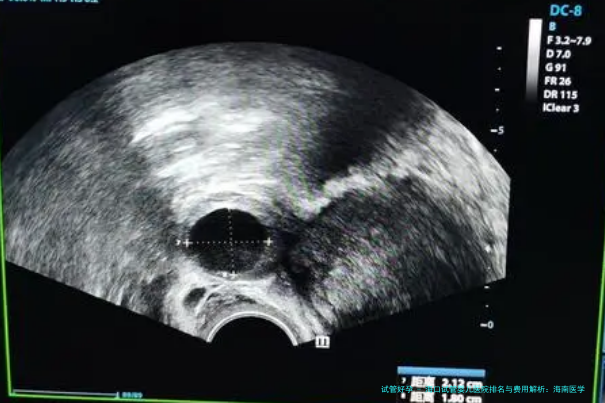

| 阴道B超下卵泡监测(单次) | 150 | 80 | 120 | 100-130 |

| 早孕B超检查(确认妊娠) | 300 | 150 | 200 | 180-250 |